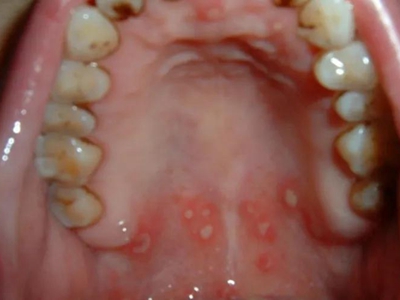

小儿口疮上腭有白色的溃疡图

小儿口疮也可发生在小婴儿的上腭,表现为白色的溃疡面,呈不规则形状,表面有灰白色坏死组织,患儿因为疼痛较重,所以常常哭闹,不爱吃奶。